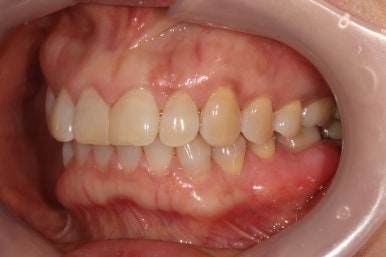

앞면, 양쪽 옆면 모두 아주 깔끔하게 유지되고 있네요!

임플란트 또한 적절히 유지되고 있고 잘 사용하고 계신 상태입니다.

신경치료와 지르코니아 크라운 치료를 받았던 치아도 뿌리끝 염증 없이 잘 사용중이시구요!